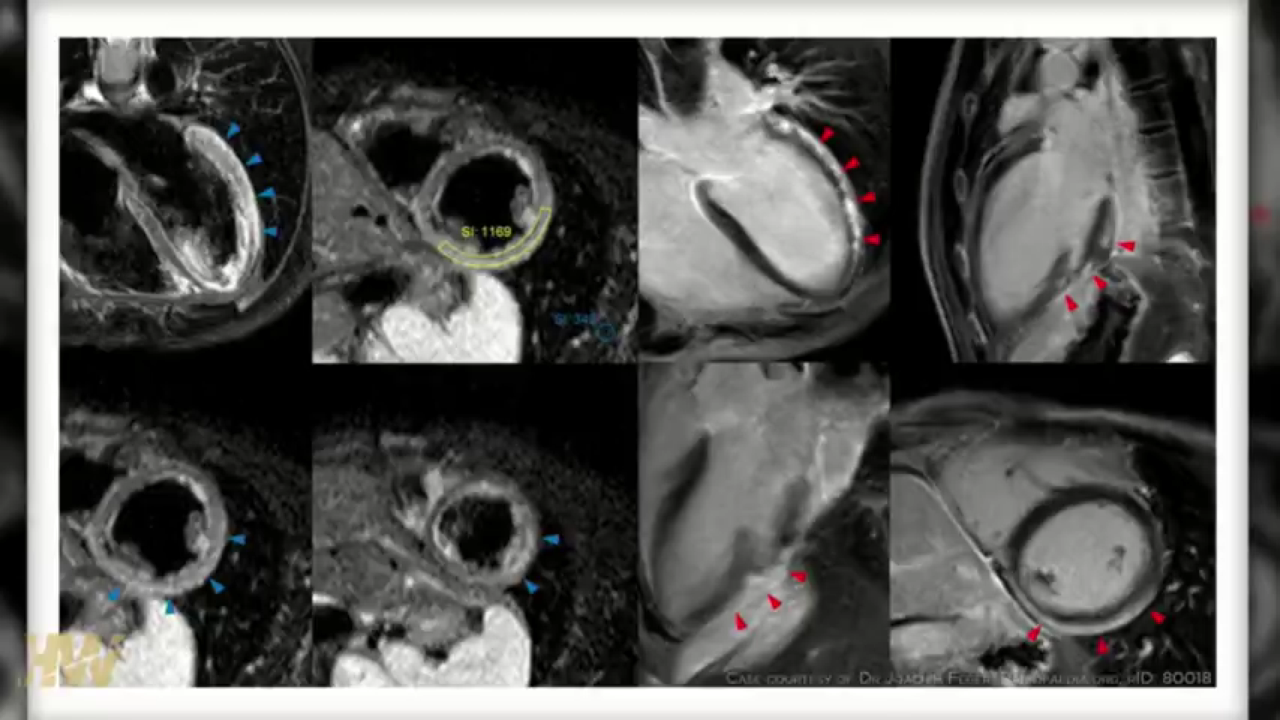

Vaxx hearts